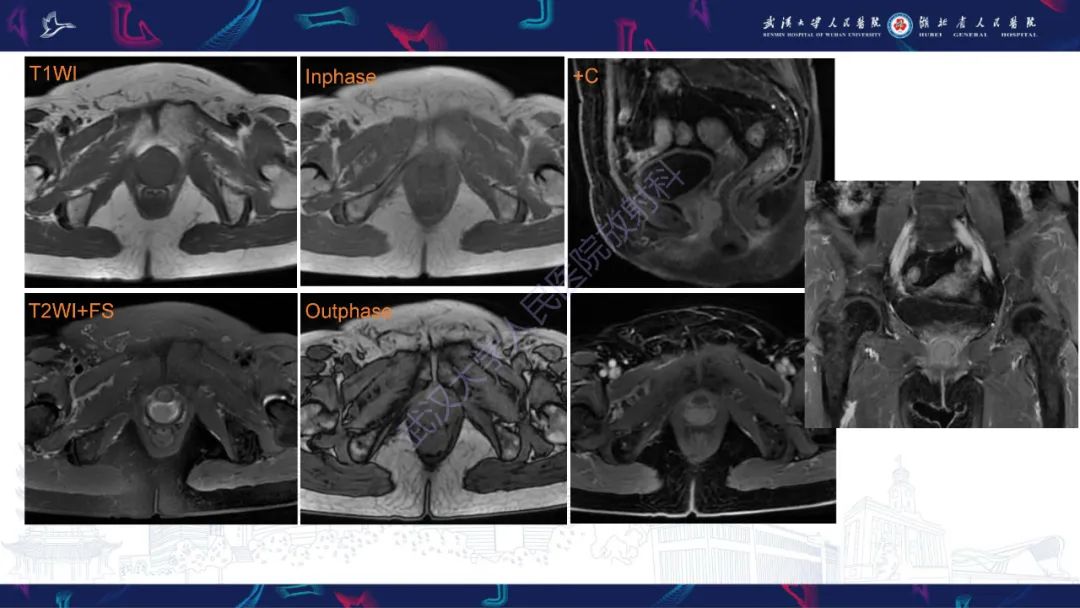

【PPT】阴道髓系肉瘤影像诊断-3